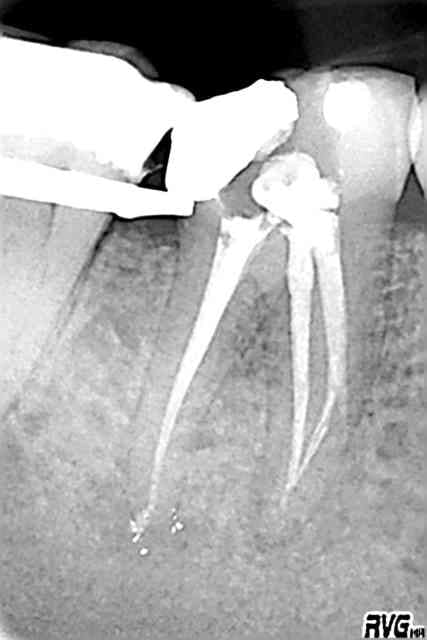

La 1è radio pour montrer la nécessité de radios excentrées, la dernière étant le résultat de l'obturation avant la reconstitution composite.